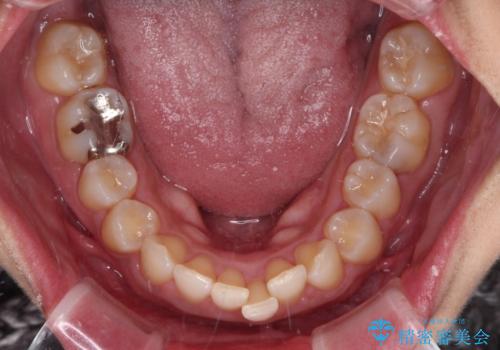

抜歯矯正で口が閉じやすく|ディープバイトと叢生を改善した症例

- 下顎前歯部には叢生が認められ、口を自然に閉じにくい状態でした。また、噛み合わせが深い「ディープバイト」の状態で、見た目だけでなく将来的な奥歯への負担も懸念されました。

口元の突出感を改善するため、上下左右の小臼歯4本を抜歯する矯正治療を計画しました。